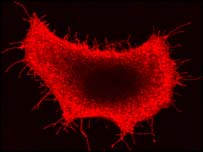

انسانی جسم کا خلیہ

انسان سمیت تمام جانداروں کے خلیے جھلیوں میں لپٹے ہوتے ہیں۔ ان ہی جھلیوں میں وہ رگیں بھی موجود ہوتی ہیں جو نمکیات یا پانی جیسے ضروری اجزاء کی ترسیل کی ذریعہ ہوتی ہیں۔ یہ رگیں صحت کے لئے اس لئے انتہائی اہم ہوتی ہیں کہ یہی تعین کرتی ہیں کہ پانی یا نمکیات جیسے ضروری اجزاء کس مقدار میں جسم میں جانے دی جائیں۔ ان ہی رگوں کے ذریعہ آنے والی پانی یا نمکیات کی زیادہ یا کم مقدار کے بغیر انسانی جسم کا کوئی خلیہ مکمل طور پر درست انداز میں کام نہیں کرسکتا۔

انسانی جسم کے خلیے پر طویل عرصے سے تحقیق کی جارہی ہے۔